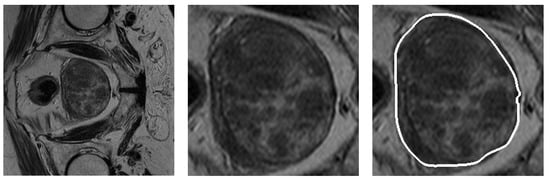

3. Validation of the Models